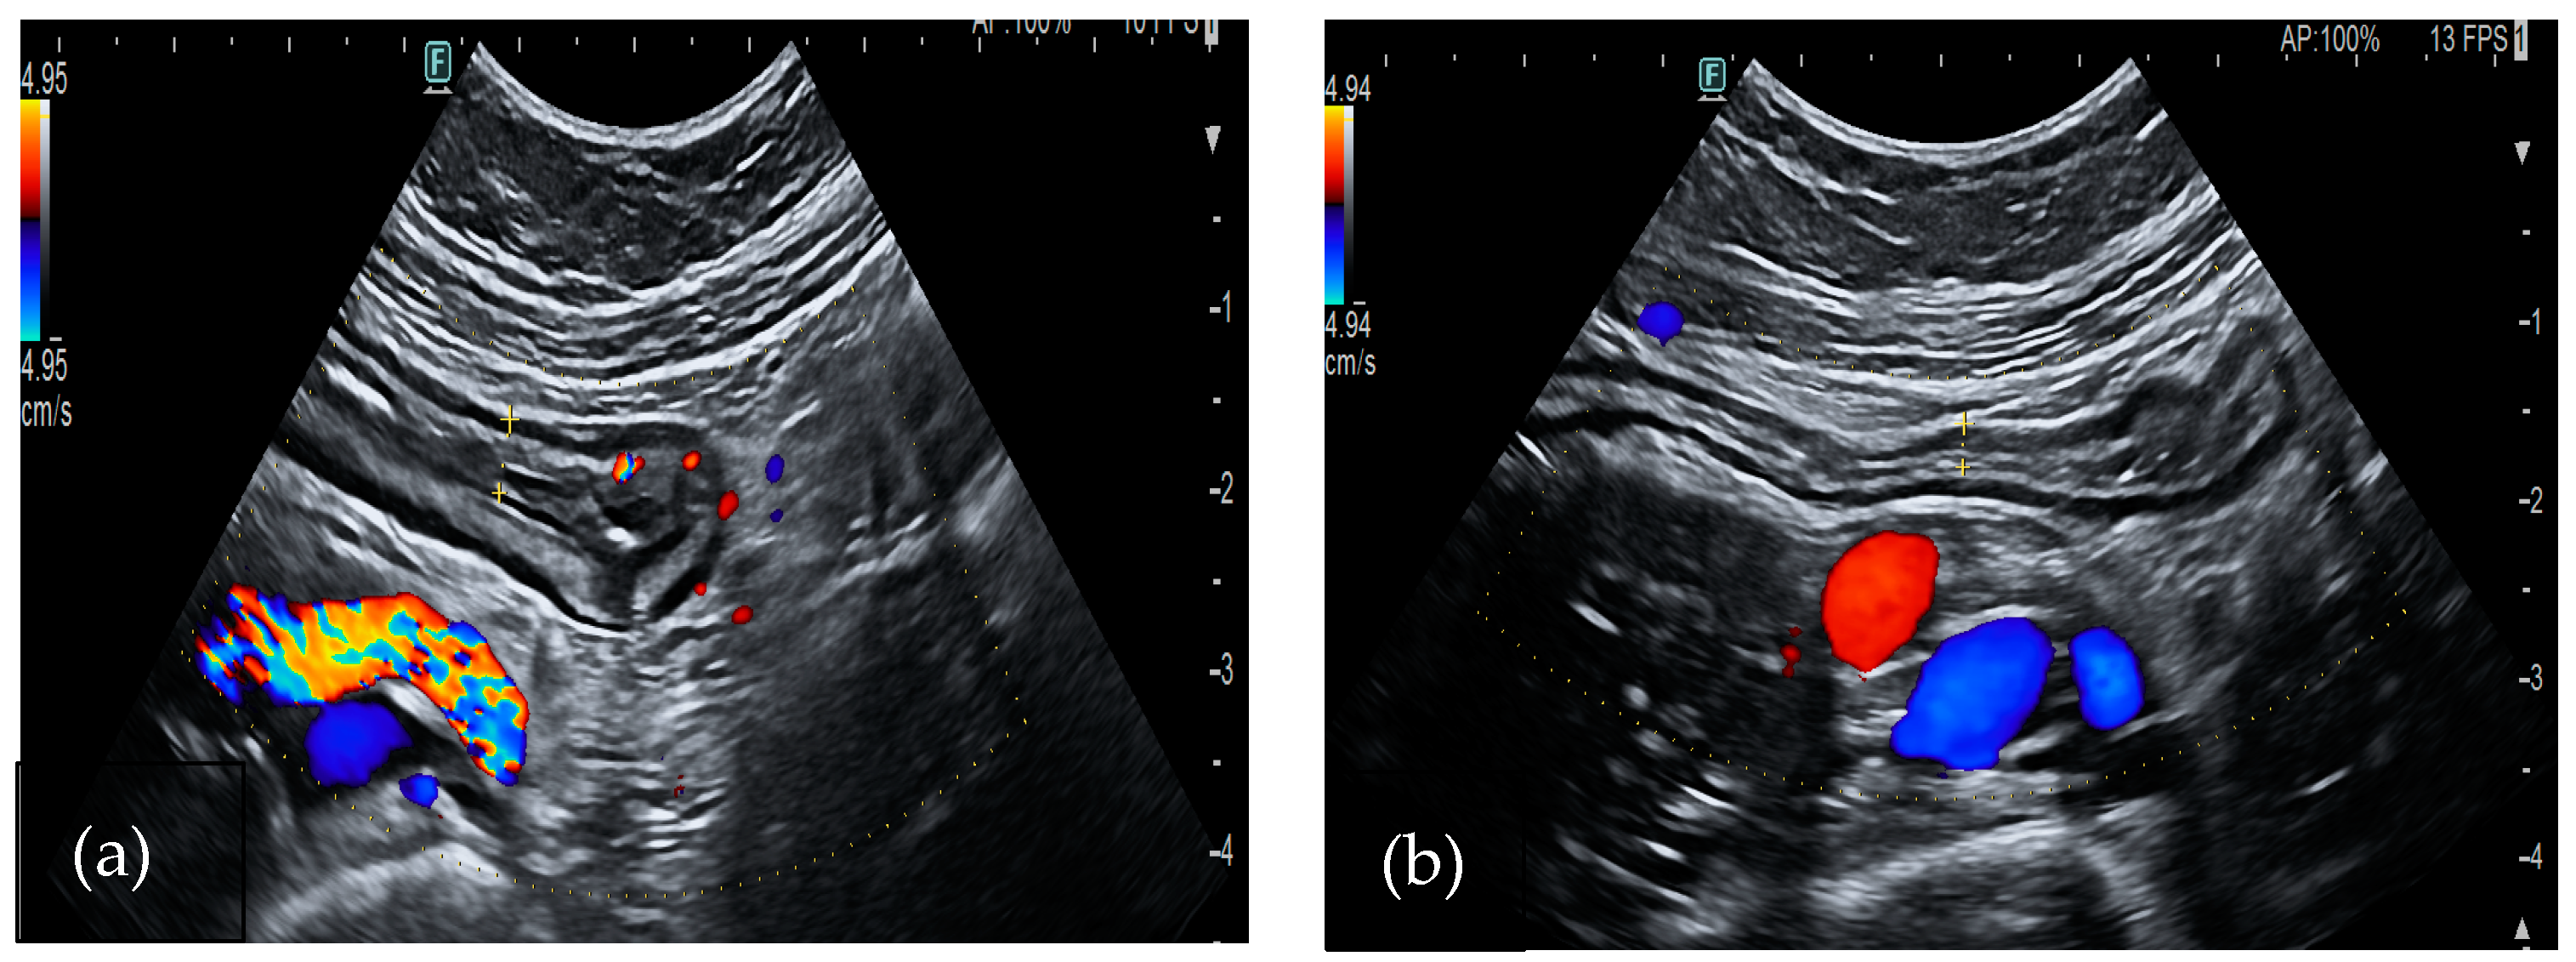

Cytomegalovirus (CMV) typically causes pancolitis in immunosuppressed patients. Moreover, in adults with UC on steroid treatment, superinfection with CMV should be suspected, especially in patients who are resistant to glucocorticoids (Figure 3). Diagnosis requires a high level of suspicion since colonoscopy biopsies are necessary [55]. Bowel ultrasound shows wall thickening and pericolic fat stranding, occasionally accompanied by free fluid. Lymph nodes enlargement is not common. These US findings are not enough to establish a definite diagnosis and IBD should be ruled out [3].

Figure 3.

A 76-year-old-male patient was diagnosed with long-term long-term left ulcerative colitis. A bowel ultrasound was performed after the onset of bloody diarrhea during mesalamine treatment. US showed diffuse colonic wall thickening: (a) 4.7 mm in the descending colon and (b) 3.6 mm in the right colon. Active vascularization (a) with free fluid (c) was also found. The biopsies performed during colonoscopy revealed a CMV infection.